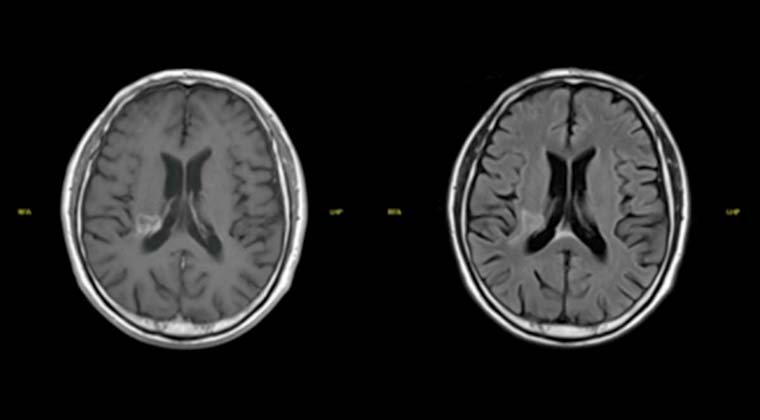

③ Случай 3:

Пациент: мужчина, 66 лет

Злокачественная опухоль носоглотки (недифференцированная некератинизирующая карцинома носоглотки)

С 102021 по 202021 проведена лучевая терапия методом VMAT (PGTV 69,96 Гр / 2,12 Гр / 33 сеанса)

После лечения проводилось непрерывное наблюдение, выявившее постепенное уменьшение опухоли в носоглотке.

При повторном МРТ 002023 отмечено исчезновение опухоли носоглотки и значительное уменьшение лимфатических узлов с ранее положительным диагнозом.

До лечения:

После лечения: